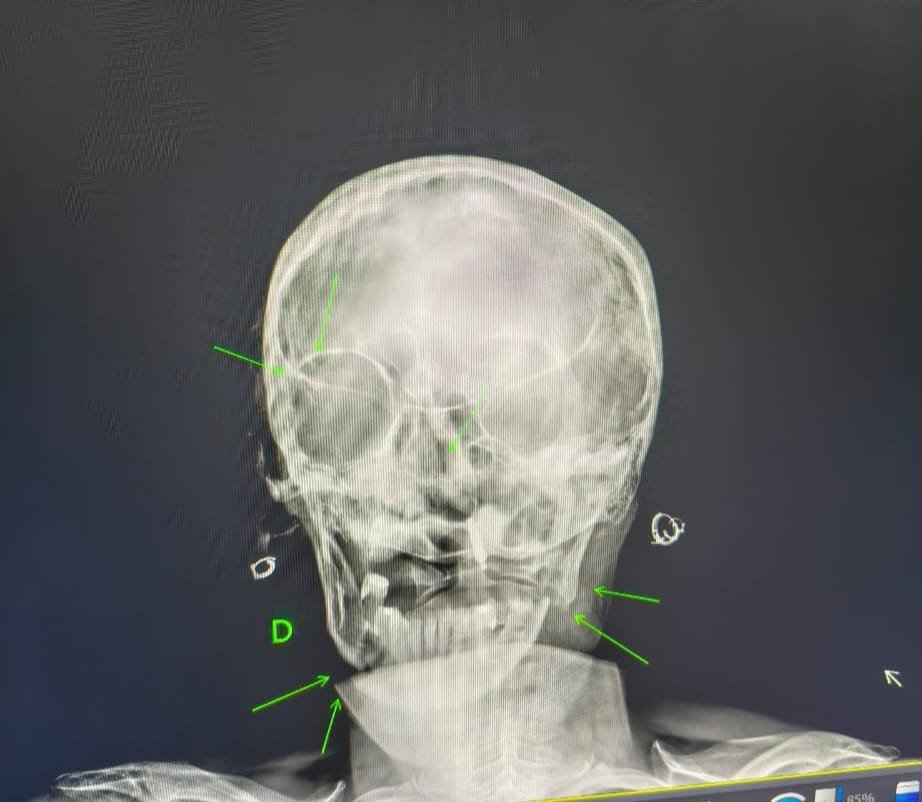

A mulher foi encaminhada inicialmente ao Hospital Municipal de Ibaté e, devido à gravidade dos ferimentos, precisou ser transferida para a UTI da Santa Casa de São Carlos. Conforme informado, ela sofreu fraturas na mandíbula, no nariz e na clavícula.